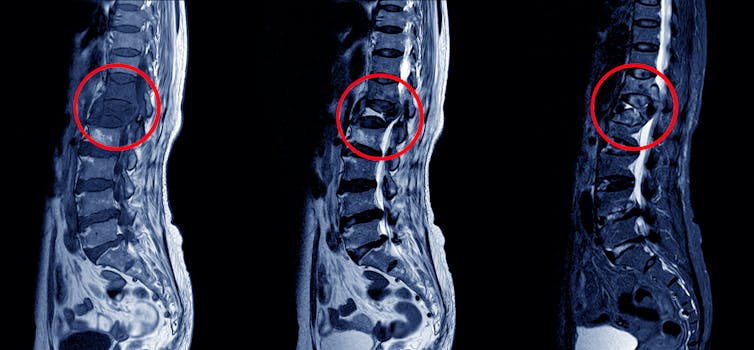

Investigations include X-rays, CT scans or MRIs and sending appropriate specimens to the laboratory to detect the TB bacterium. The type of specimen that should be sent depends on the organ system involved. For example, in the case of lymph node TB, a biopsy (tissue specimen) of the lymph node should be sent to the laboratory; in the case of pleural TB, pleural fluid should be sent for testing.